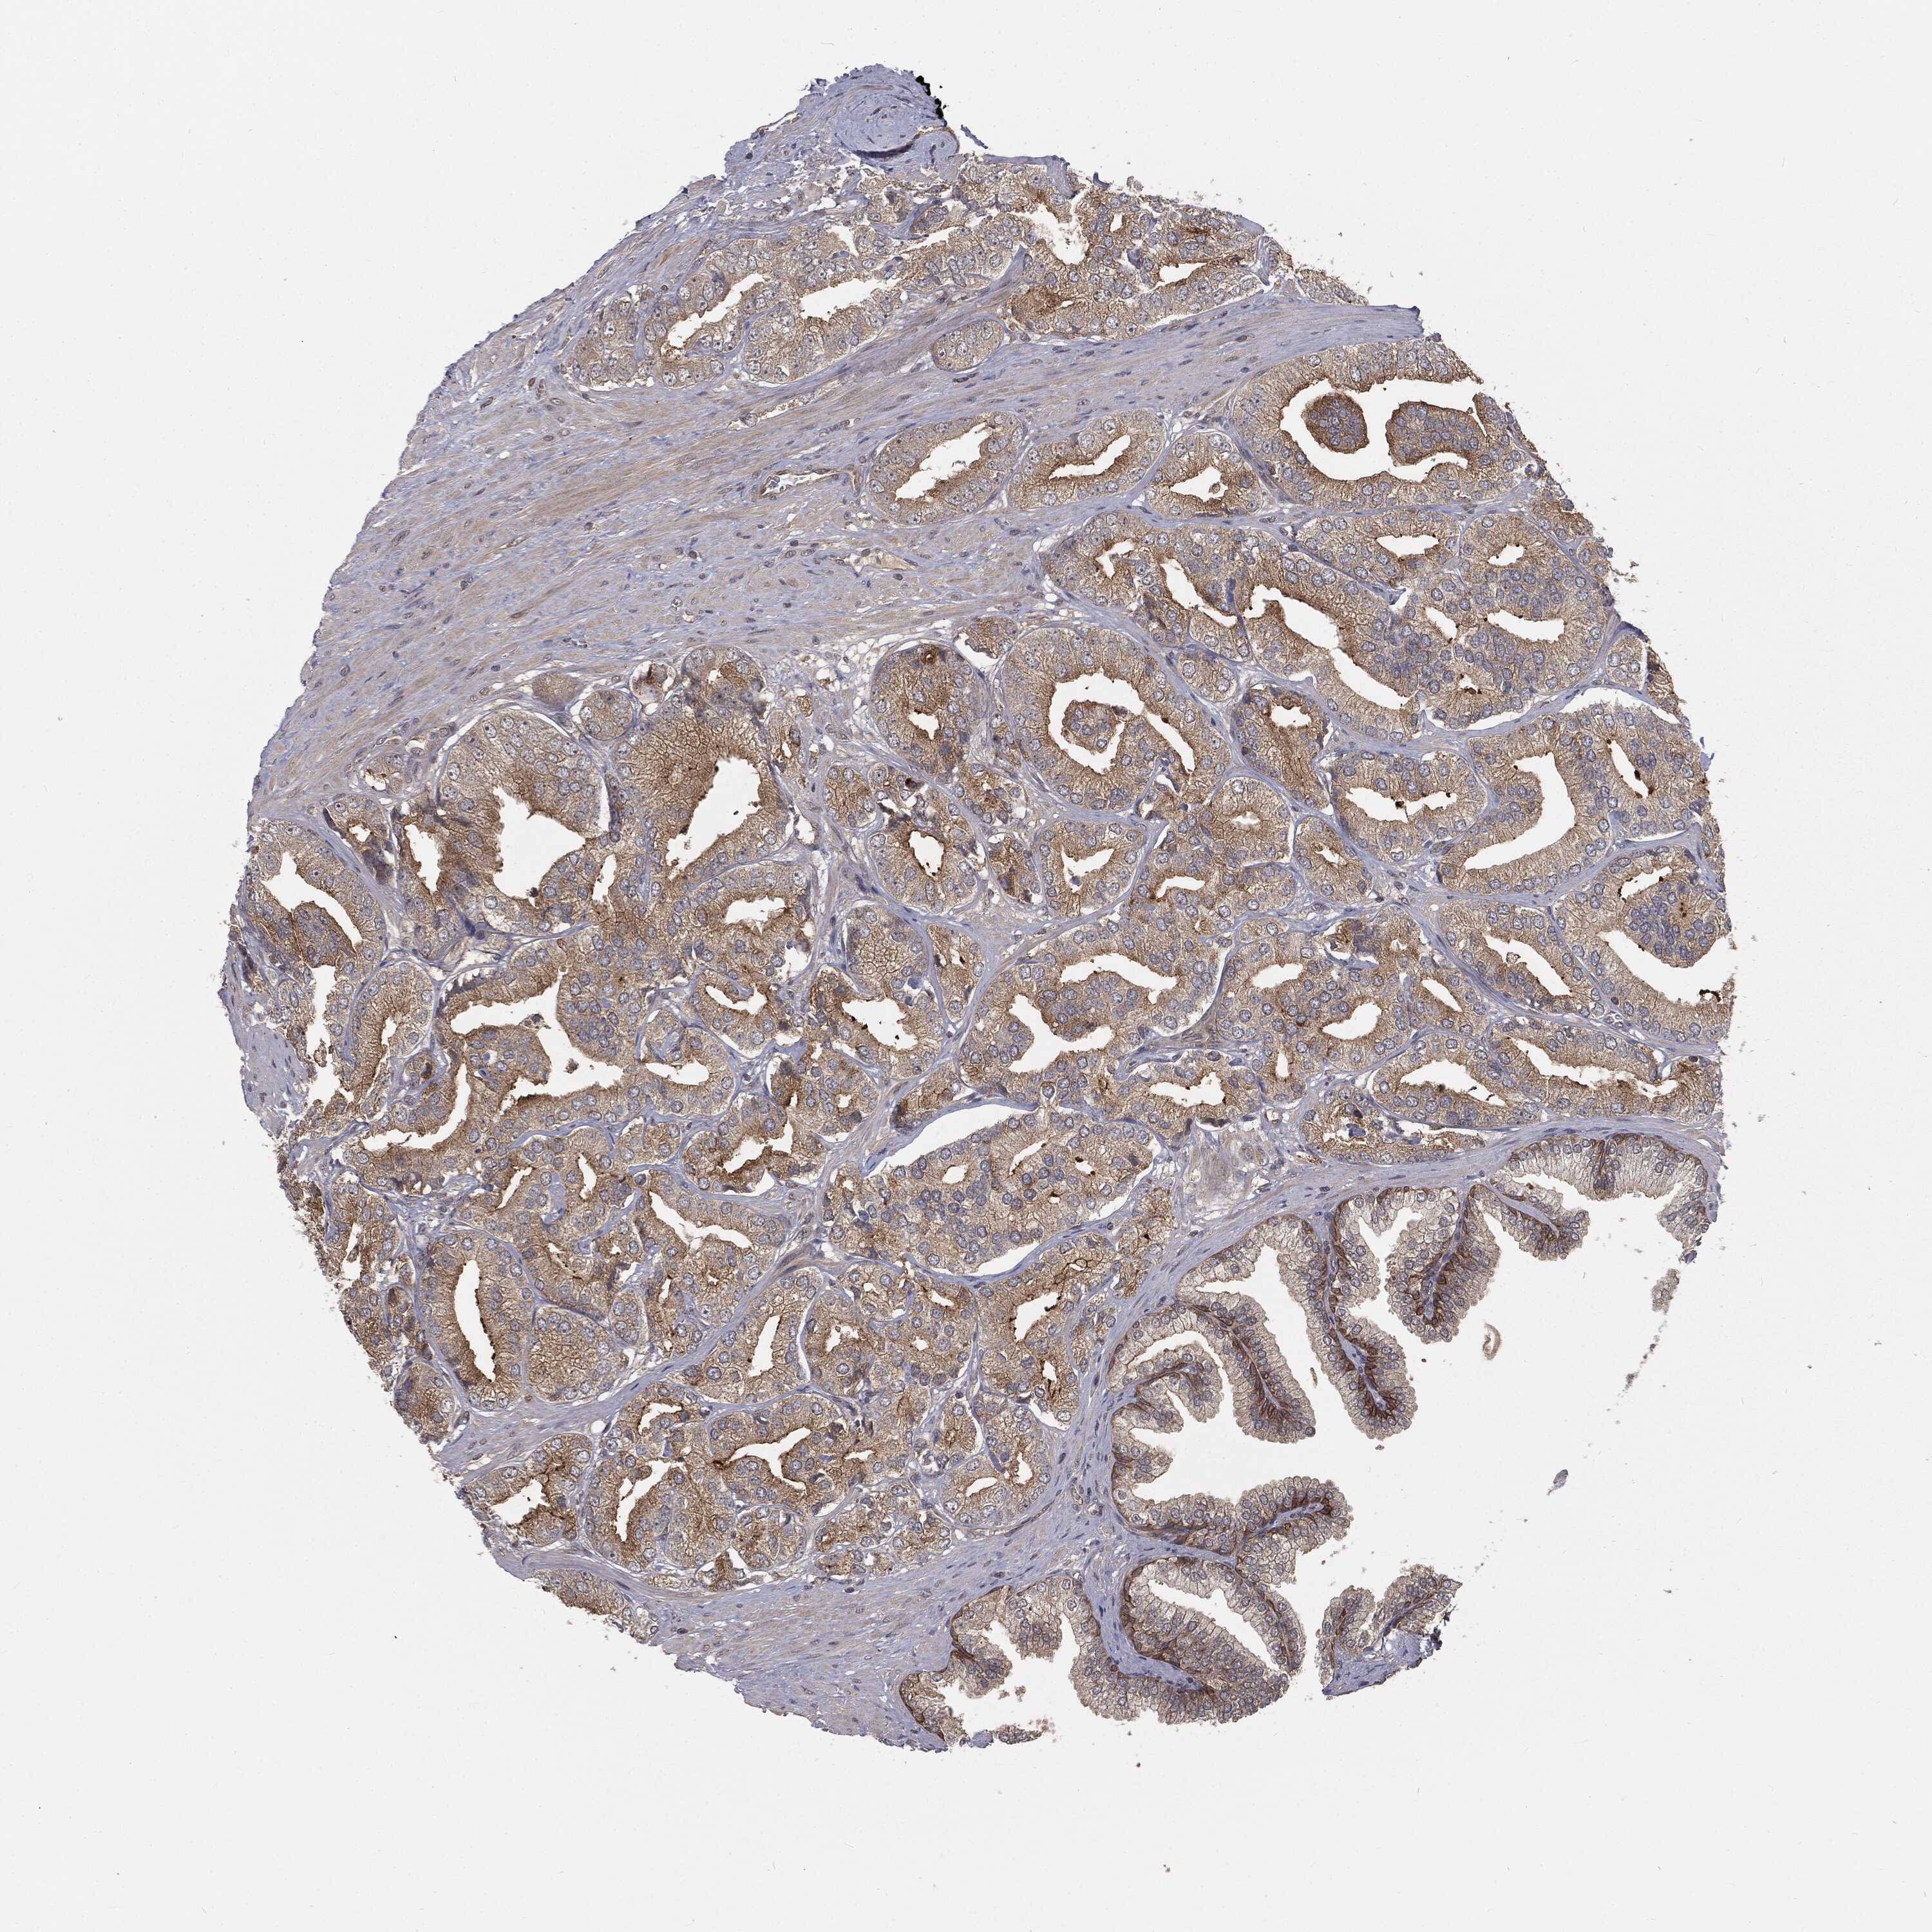

PROSTATE CANCER - Protein expressioni

A mouse-over function shows sample information and annotation data. Click on an image to view it in a full screen mode. Samples can be filtered based on level of antibody staining by selecting one or several of the following categories: high, medium, low and not detected. The assay and annotation is described here.

Antibody stainingi

Antibody staining in the annotated cell types in the current human tissue is reported as not detected, low, medium, or high, based on conventional immunohistochemistry profiling in selected tissues. This score is based on the combination of the staining intensity and fraction of stained cells.

Each image is clickable and will lead to virtual microscopy that enables deeper exploration of all samples and also displays staining intensity scores, fraction scores and subcellular localization as well as patient and tissue information for each sample.

Antibody HPA032114

Antibody HPA057352

Antibody CAB034296

Staining

High

Medium

Low

Not detected

Intensity

Strong

Moderate

Weak

Negative

Quantity

>75%

75%-25%

<25%

None

Location

Nuclear

Cytoplasmic/membranous

Cytoplasmic/membranous,nuclear

Adenocarcinoma, NOS

Adenocarcinoma, High grade

Adenocarcinoma, Low grade